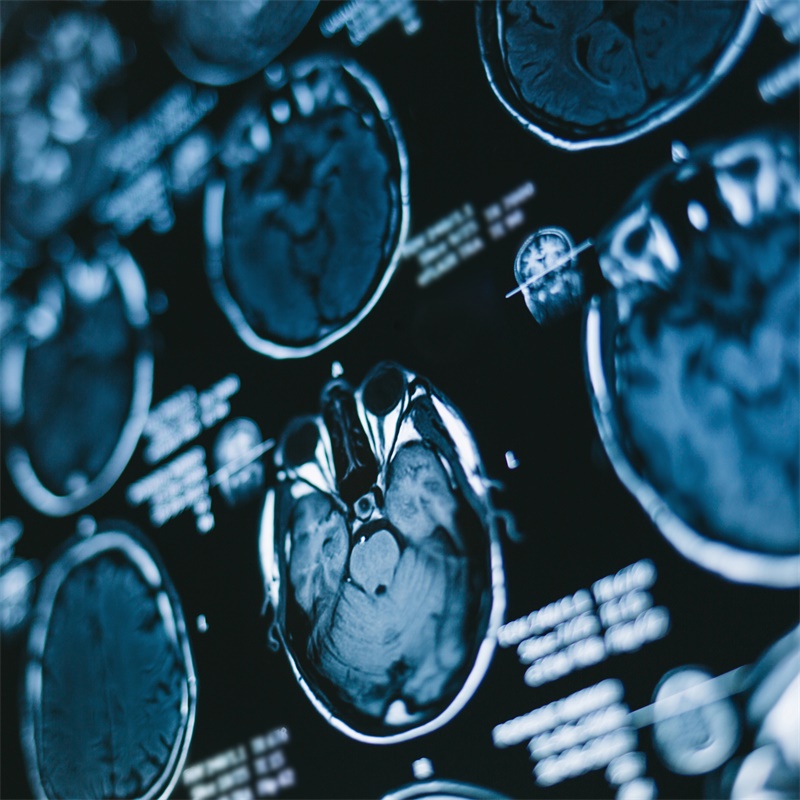

癫痫是一种中枢神经系统(神经系统)疾病,其中大脑活动变得异常,导致癫痫发作或出现异常行为、感觉,有时甚至丧失意识。任何人都可能患上癫痫症。癫痫影响全部种族、民族背...

癫痫 是国际上四常见的神经系统疾病,影响6500万人。癫痫的主要症状是不可评估和反复发作。如果癫痫患者至少发作过两次,且不能被归为低血糖等其他原因,医生就会对其进行诊...